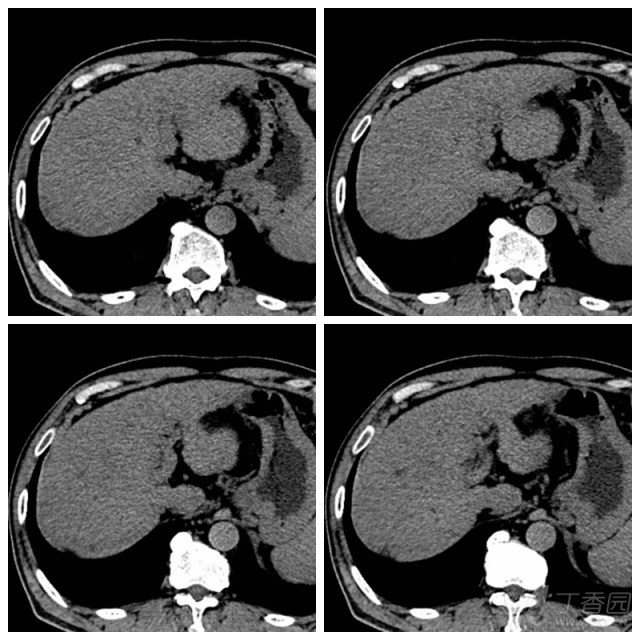

肝癌:增强ct,典型"快进快出".